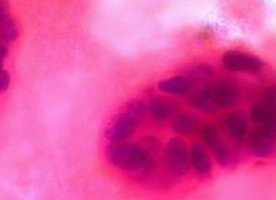

This therapeutic resistance has been associated with overactivation of the PI3K/AKT/mTOR pathway. Afinitor works to target the mTOR pathway in cells. mTOR is a protein that acts as an important regulator of tumour cell division, blood vessel growth and cell metabolism.